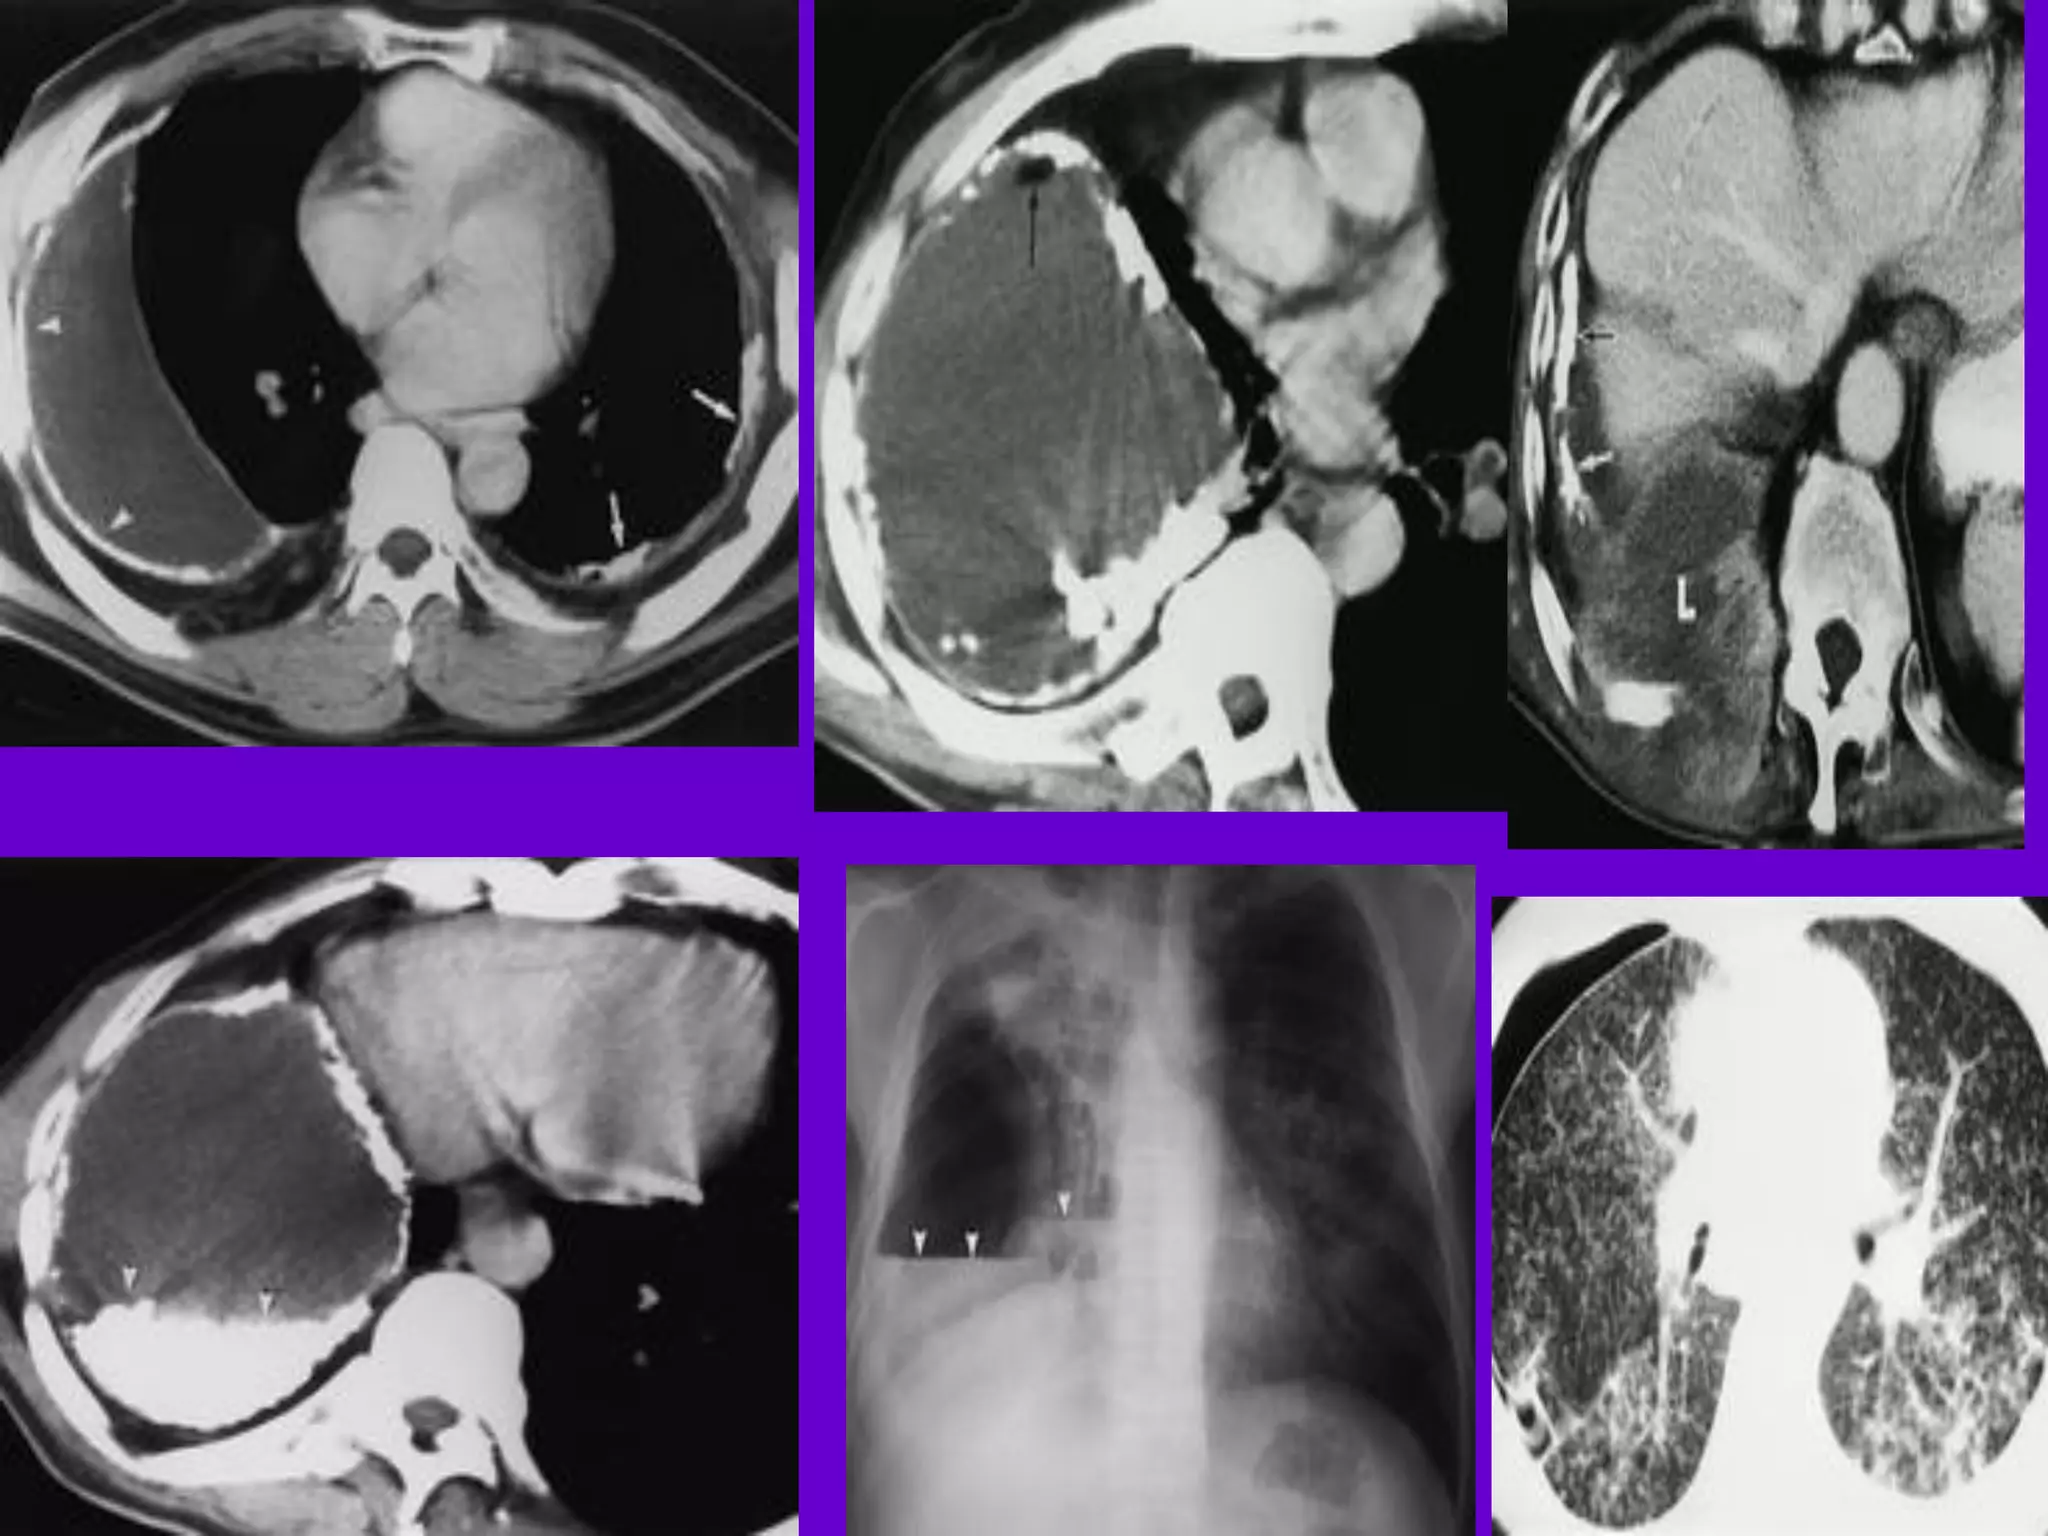

CT Scan andMRI Scan in the diagnosis of TB 􀂄 The advent of CT and MRI imaging in the last two decades has redefined the approach in analysis of various diseases including TB.* 􀂄 CT and MRI have shown several advantages over conventional radiology in early diagnosis and follow-up of TB in different parts of the body. *Buxi TBS Indian J Pediatr 2002;69:965-972

Pulmonary TB : LobarPneumonia 􀂄 CT is superior than plain CXR in picking up the consolidation, atelectasis and the hilar LN thereby making the diagnosis easy. 􀂄 MRI reveals some of these changes, however, CT is the diagnostic modality of choice in such cases. 􀂄 Bronchopneumonia 􀂄 On CT it is usually B/L and widespread, not always symmetrical involvement of lungs. 􀂄

Hilar and Mediastinal Lymphadenopathy CTand MRI depict the hilar and mediastinal LN equally well. 􀂄 Calcification in the nodes is however better seen on CT. 􀂄 Necrosis is seen as focal areas of low attenuation on a CECT. 􀂄 On MRI focal necrosis is seen as areas of increased signal intensity on T2W images. 􀂄 EBTB 􀂄 HRCT is sensitive in the detection of early endobronchial spread of disease. 􀂄

Miliary TB 􀂄 Earliestform of miliary TB is detectable on HRCT. 􀂄 Coalescing nodules result into patchy irregular opacities and HRCT shows this variation effectively and has been described as “snowstorm appearance”. 􀂄 HRCT shows cavitation, which is not evident on plain CXR. Pleural Effusion 􀂄 􀂄 CT is sensitive to diagnose and define even minimal pleural effusion/pleural calcification. 􀂄 Pleural fluid is seen on inversion recovery MR images as areas of increased signal intensity along the inner aspects of the chest wall.